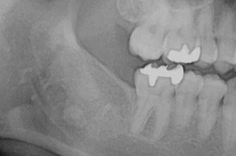

• 抜歯2週間後の状態

抜歯した部分は、徐々に骨が出来上がってきます。

抜歯後、半年程で骨は出来上がります。

健康保険適用のため治療費は約4,000円(3割負担)。

治療期間は、抜歯後1週間ほどで抜糸を行い問題なければ終了。

治療のリスクは、術後の疼痛(ドライソケット)・術後の感染・下歯槽神経麻痺・上顎洞との交通などがあります。